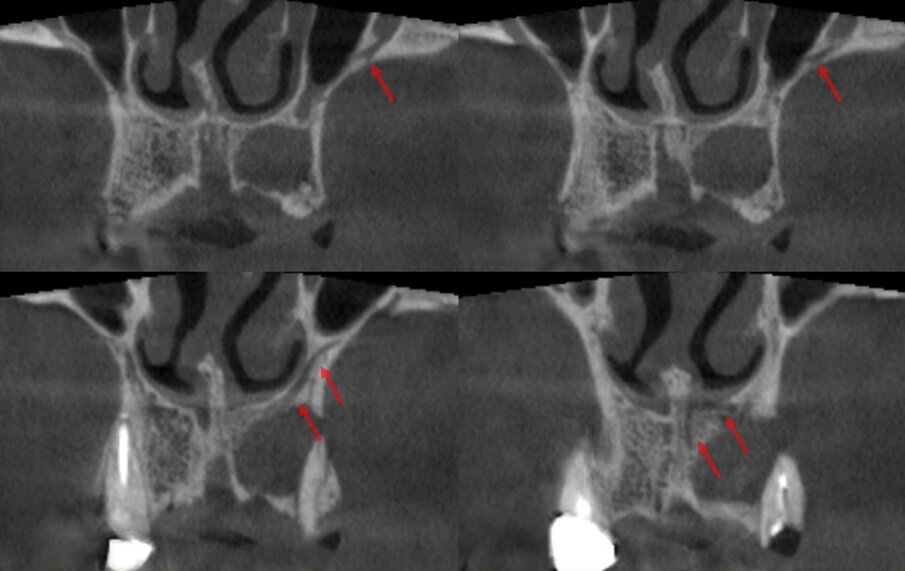

Il termine Canalis Sinuosus (CS) descrive l’andamento a doppia curvatura di quest’ultimo che scorre per circa 55 mm attraverso il mascellare ed è caratterizzato da un sottile osso sovrastante che lo rende più suscettibile a lesioni in caso di trauma. Per questo motivo è considerato un ramo importante del nervo infraorbitario (ION), al suo interno decorrono il nervo alveolare superiore anteriore (ASAN) e vene ed arterie corrispondenti. Infatti, il nervo alveolare antero-superiore (ASAN) è una divisione del ramo mascellare del nervo trigemino che segue un decorso intraosseo nel CS attraverso il mascellare anteriore per innervare gli incisivi ed i canini (Fig. 3). Nel suo terzo finale il nervo alveolare antero-superiore è caratterizzato dalla presenza di molteplici connessioni nervose che possono garantire, in caso di danno, la percezione della sensibilità della zona innervata. La presenza di un CS e di forami accessori (Fig. 4) è spesso ignorata nella pratica chirurgica poiché queste varianti anatomiche possono solo essere rilevate da un attento esame delle immagini radiologiche pre-operatorie, inoltre la loro presenza potrebbe influire direttamente sul successo terapeutico1-5.

Una paziente di 62 anni, ASA 1 si rivolge alla nostra attenzione per richiedere una riabilitazione dell’arcata mascellare superiore essendo portatrice di protesi mobile totale. L’esame radiologico iniziale evidenzia una marcata atrofia ossea quindi viene progettato l’inserimento di 8 impianti dopo elevazione bilaterale dei seni mascellari al fine di realizzare un a protesi tipo Toronto-Bridge. Trascorsi 8 mesi dai sinus lift e dopo aver accertato la totale guarigione dei siti innestati con una CBCT viene eseguito l’intervento implantare in anestesia locale, sotto profilassi antibiotica, con chiusura dei lembi per prima intenzione e senza eseguire procedure di carico immediato. La paziente viene quindi controllata regolarmente ed a distanza di 7 giorni manifesta una sintomatologia algica localizzata alla zona 1.1 che inizialmente appariva compatibile con il normale decorso post-operatorio. Successivamente a 15 giorni la situazione era nettamente peggiorata trasformandosi in dolore localizzato e persistente con acutizzazioni che la paziente descriveva come “scosse elettriche” o “stilettate”. A questo punto è stata eseguita una nuova analisi della CBCT postoperatoria (Fig. 5) al fine di indagare in maniera più approfondita tale zona, l’analisi delle immagini ha evidenziato la presenza di un CS destro compresso dall’apice dell’impianto in posizione 1.1 (Figg. 6, 7). Tale condizione veniva subito riconosciuta compatibile con la sintomatologia della paziente e si procedeva a rimuovere e sostituire la fixture con una di lunghezza inferiore che non interessasse il decorso del CS (Fig. 8). Veniva quindi prescritta una terapia farmacologica post-operatoria comprensiva di antibiotici, antinfiammatori ed integratori di complessi vitaminici B. La paziente è stata controllata giornalmente manifestando un graduale miglioramento fino a scomparsa della sintomatologia algica a 15 giorni.

Fig. 3 - Decorso del CS evidenziato nella ricostruzioni coronali di una CBCT.

Nella moderna chirurgia odontoiatrica la CBCT ha assunto un ruolo predominante nella valutazione pre-operatoria delle riabilitazioni di pazienti parzialmente e totalmente edentuli fornendo immagini affidabili ad alta risoluzione di gran lunga superiori alle precedenti tecnologie bidimensionali. È quindi facilmente capibile come un’attenta valutazione delle immagini pre-operatorie sia necessaria al fine di individuare l’eventuale presenza di un CS: l’immagine migliore per evidenziare il CS è la ricostruzione Panorex (Fig. 5), ricavata dalle immagini assiali, oppure l’immagine coronale (Fig. 3). Qui infatti possiamo evidenziare l’origine del CS dal nervo infraorbitario, la doppia curva a livello dell’apertura piriforme ed il decorso coronale fino all’emergenza nel forame accessorio. Da un punto di vista radiologico tuttavia bisogna ricordare che tutte le ricostruzioni (specialmente quelle con panorex e cross-sections/parassiali) possono portare alla formazione di artefatti quindi il nostro sospetto diagnostico andrà verificato sulle immagini assiali originali ripartendo dal forame infraorbitario e seguendo il percorso fino all’emergenza palatina (se radiologicamente evidente). Gli aspetti chiave da ricercare nelle immagini assiali sono la radiotrasparenza del contenuto del CS circondata da un orletto radiopaco come tipico di un canale infraosseo contenente un fascio vascolo-nervoso.